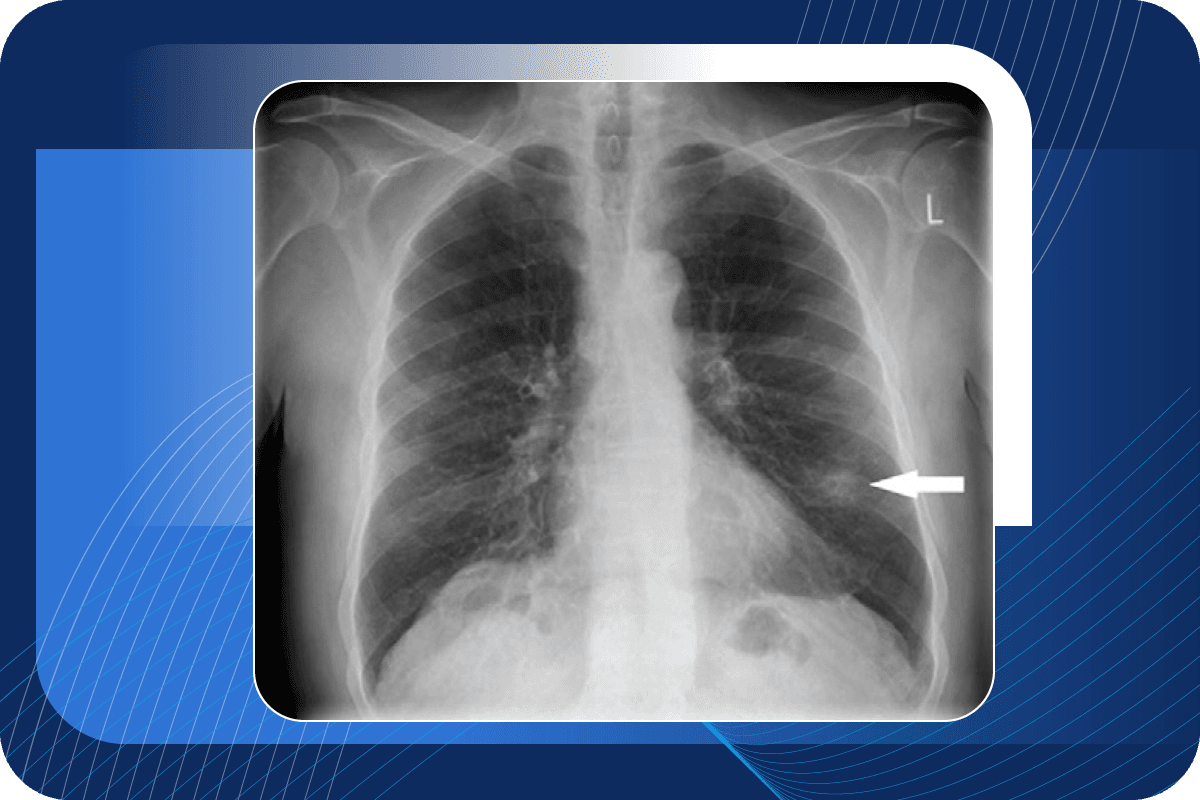

Commonly called a “spot on the lung” or a “shadow,” a nodule is a round area that is more dense than normal lung tissue. It shows up as a white spot on a CT scan. Lung nodules are usually caused by scar tissue, a healed infection that may never have made you sick, or some irritant in the air. Sometimes, a nodule can be an early lung cancer.

One or more lung nodules were seen on your recent chest x-ray or CT (“CAT”) scan.